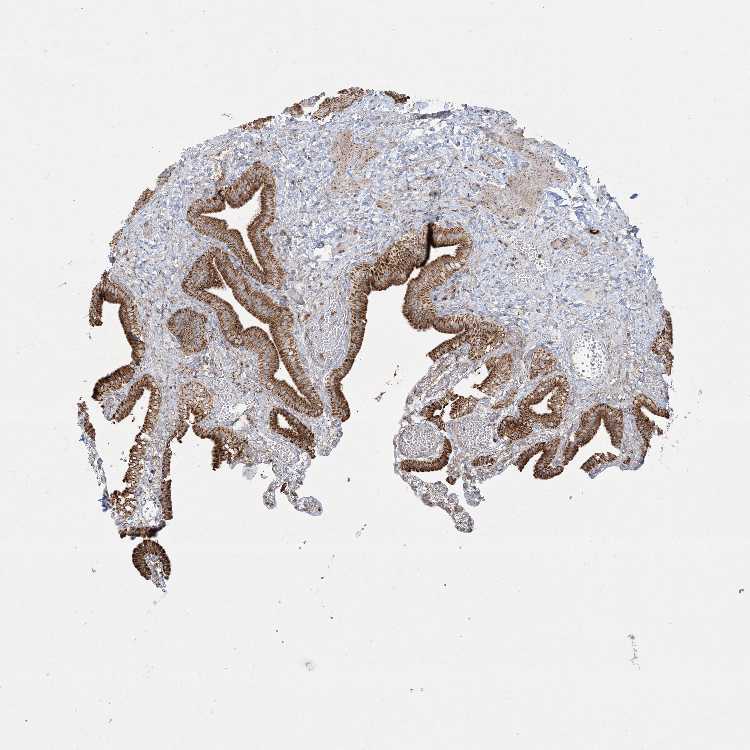

BEND4